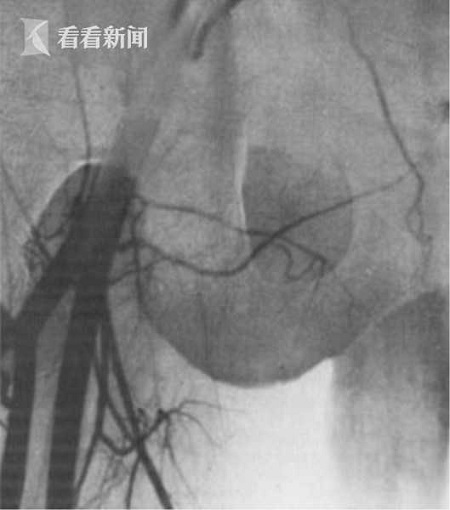

男子沒“蛋蛋”無法生育 兄長自愿捐助移植成功

近日,在塞爾維亞的一家醫(yī)院進(jìn)行了一場(chǎng)不同尋常的手術(shù)。一名36歲男子因先天沒有睪丸,導(dǎo)致其無法生育,為了一圓其當(dāng)爸爸的夢(mèng)想,雙胞胎哥哥自愿捐助一顆睪丸。經(jīng)過國際醫(yī)療團(tuán)隊(duì)長達(dá)6小時(shí)的高風(fēng)險(xiǎn)手術(shù)后,睪丸移植宣告成功,讓該名男子終于有了生育能力。

綜合外媒報(bào)道,該名36歲的塞爾維亞男子和哥哥是同卵雙胞胎,遺憾的是在母體胎盤中時(shí),細(xì)胞沒有完整分裂,導(dǎo)致在出生時(shí)就沒有睪丸。雖然當(dāng)哥哥的自愿捐助一顆睪丸,但是由于手術(shù)難度堪稱世界級(jí),遲遲沒有醫(yī)生敢動(dòng)刀。直到近日,一位美國名醫(yī)率隊(duì)飛到塞爾維亞,為他進(jìn)行長達(dá)6小時(shí)的手術(shù),移植才宣告成功。

這位名叫喬爾杰維奇的醫(yī)生任職于美國紐約西奈山醫(yī)院性別重置???,上周率領(lǐng)國際醫(yī)療團(tuán)隊(duì)飛抵塞爾維亞首都貝爾格萊德,親自操刀實(shí)施手術(shù)。

手術(shù)期間,醫(yī)療團(tuán)隊(duì)必須同時(shí)將雙胞胎兄弟的陰囊切開,進(jìn)行睪丸移植,并在極為有限的時(shí)間內(nèi),將陰囊內(nèi)的兩根動(dòng)脈、兩根寬不到兩毫米的靜脈成功縫合。

另據(jù)專業(yè)人士介紹稱,一旦把睪丸從捐贈(zèng)者體內(nèi)取出后,必須在之后的2到4個(gè)小時(shí)內(nèi),重新“接上線”。睪丸在無血液注入的情況下,最多只能存活6個(gè)小時(shí)。

手術(shù)后,這對(duì)匿名的塞爾維亞兄弟恢復(fù)情況良好,各項(xiàng)生理指標(biāo)也重回正常水平。由于捐贈(zèng)者和受捐贈(zèng)者為雙胞胎,未引發(fā)排異反應(yīng)。